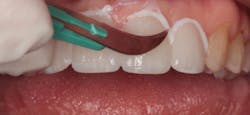

In 2016, she decided that she wanted to replace her veneers with the new bleach-shaded materials available today. In Figure 1, you can see her veneers as they appeared after nineteen years. Note the excellent tissue health and minimal tissue recession. There was a small fracture in the disto-incisal corner of the right central incisor. The incisal view at this date can be seen in Figure 2.

Figure 2: Incisal view of the patient’s porcelain laminate veneers placed in 1997 as seen in 2016